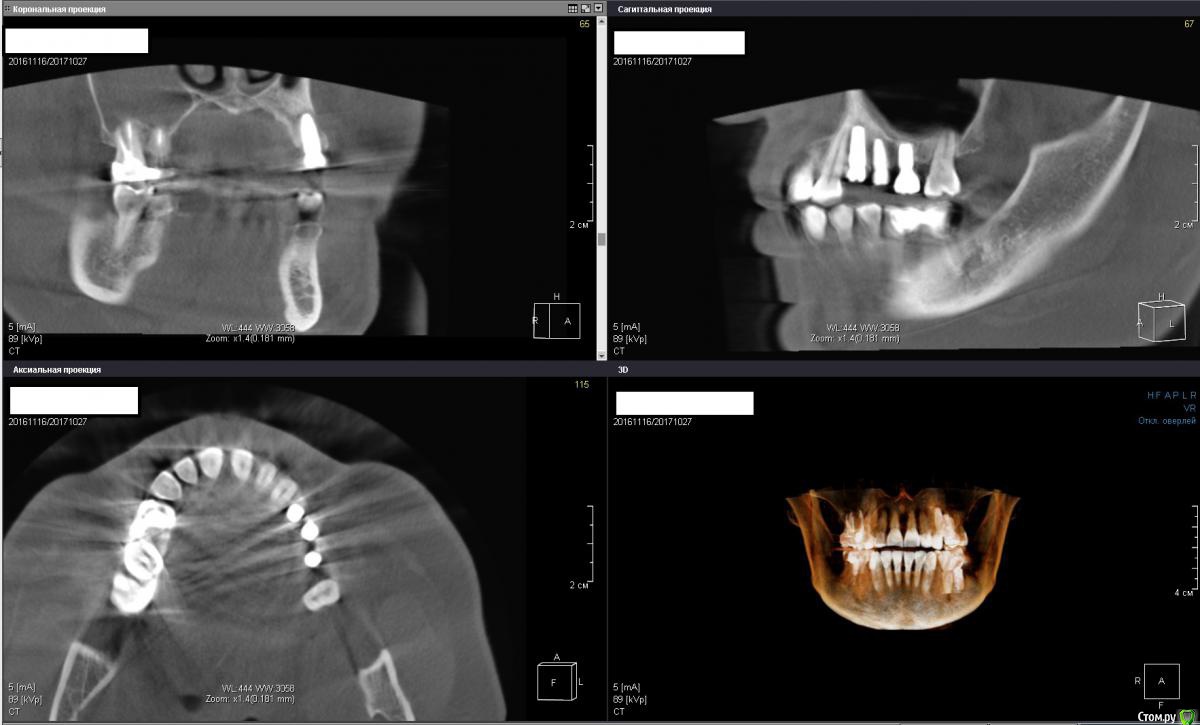

Irouil Опубликовано 2 ноября, 2017 Поделиться Опубликовано 2 ноября, 2017 Коллеги, очень прошу подсказки. Буду очень признателен за помощь. Вопрос пл 2.4 (первый товарищ из 3). Клиника такова: одномоментно с удалением был установлен винт, все проходило без эксцессов, через 4 месяца закрутил формики на 25 Нсм, при выкручивании 2.4 вышел вместе с фдм (моя глупость, имхо). Оставил на месяц, через месяц пилотным сверлом посерединке прошелся и поставил такой-же винт обратно, торк нормальный (точно не помню), все хорошо заживало. Где-то через месяц после установки случился казус - вестибулярно от фдм видимо что-то под манжету попало, пациенка затянула что-то с визитом, когда пришла сделал разрез по переходой, получил гной, перкуссия имплантата во всех направлениях чистая. Сегодня 5,5 месяцев с переустановки, имплантат звенит при перкуссии, снаружи все выглядит прекрасно (пальпация везде чистая, манжеты выглядят гладко, розово) НО! При выкручивании формика с пальчикового торка пациентка реагирует (говорит, что больно, но может просто чувствует - тут такие страхи перед всем, даже при анестезиях всегда слезы и квазиистерики). Притом, я уже не выдержал и под анестезией дал торк 15 на фдм туда и обратно - все чисто. Кт обе актуальные, вторая с толщиной среза 2 мм примерно. Че делать то? Планируется общая конструкция 2.4, 2.5, 2.6 Ссылка на комментарий

Irouil Опубликовано 2 ноября, 2017 Автор Поделиться Опубликовано 2 ноября, 2017 Ах, да, тройка тоже при перкуссиях/обдувах чистая как слеза младенца Ссылка на комментарий